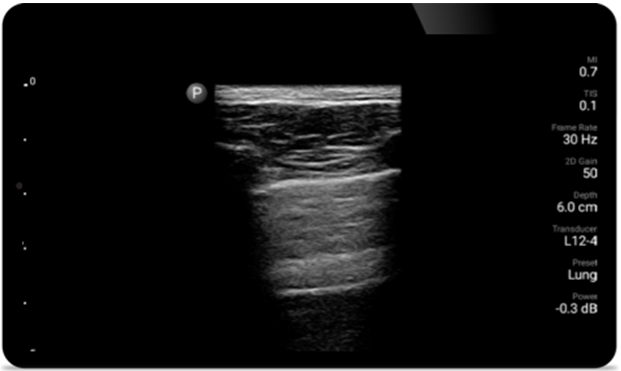

Respire con mayor facilidad con Lumify

Lumify puede ayudar a evaluar a los pacientes más rápido y a mejorar la precisión en el diagnóstico de las causas comunes de disnea y otras afecciones pulmonares.